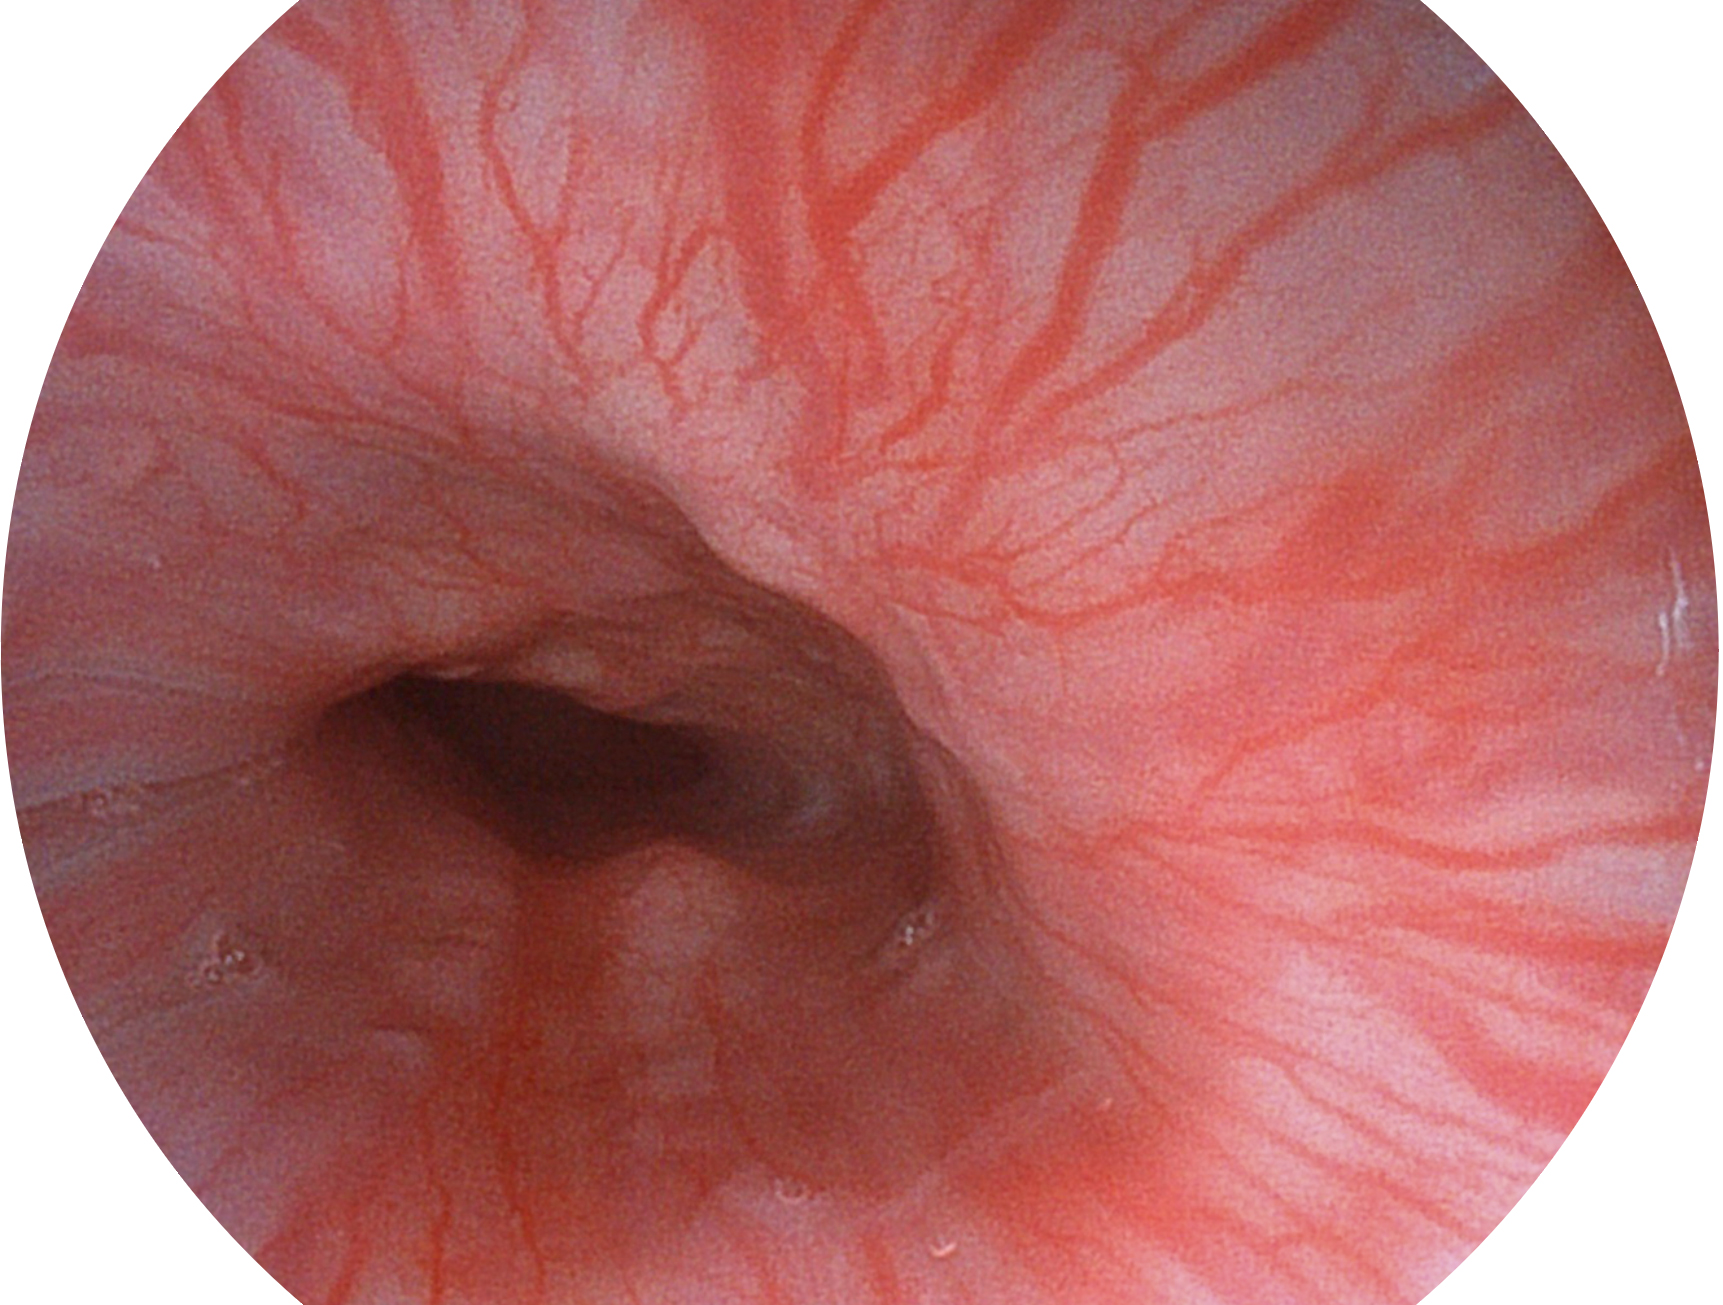

诸侯快讯官网新开发的内镜染色技术,主要是基于多波长LED 光源的开发,VLS-55Q 四波长LED 光源是由四个不同颜色的LED光按照相应照明模式所规定的特定发光比例进行合束后形成,合束后形成的照明光的光谱由红光、绿光、蓝光及蓝紫光这四个不同的波段范围构成。具有更高光谱自由度,通过光谱比例的控制,实现了聚谱成像技术,英文全称为“Spectral Focused Imaging, SFI”,缩写为“SFI”和光电复合染色成像技术,英文全称为“Versatile Intelligent Staining Technology, VIST”,缩写为“VIST”。